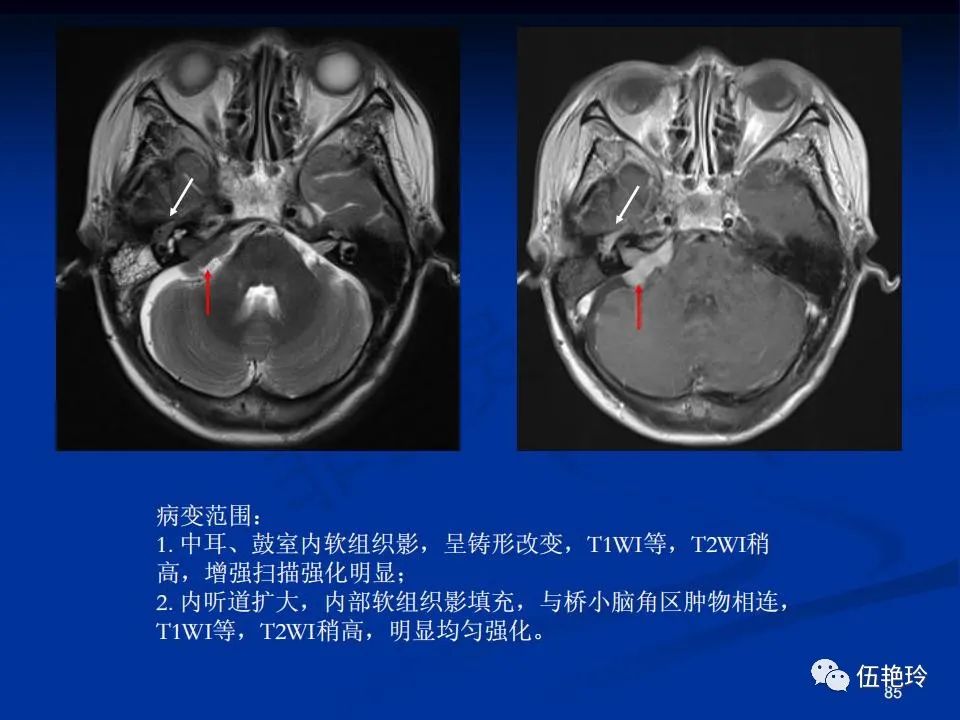

耳与面神经的解剖